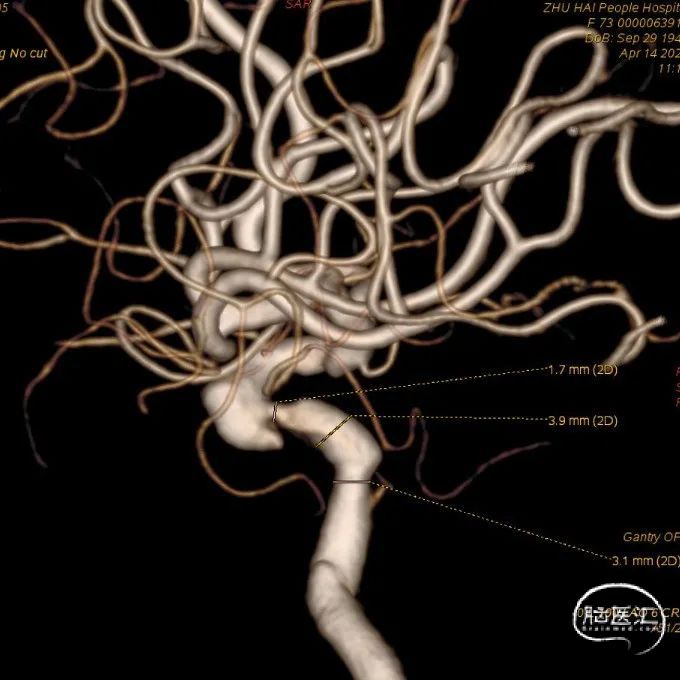

术前影像

左侧颈内动脉重建(左侧狭窄及扩张较右侧更甚)

1. 患者双侧颈内动脉多发瘤样扩张及狭窄,其中左侧为甚,破裂出血及出现缺血事件风险较高

2. 拟单枚Surpass Streamline覆盖长段病变